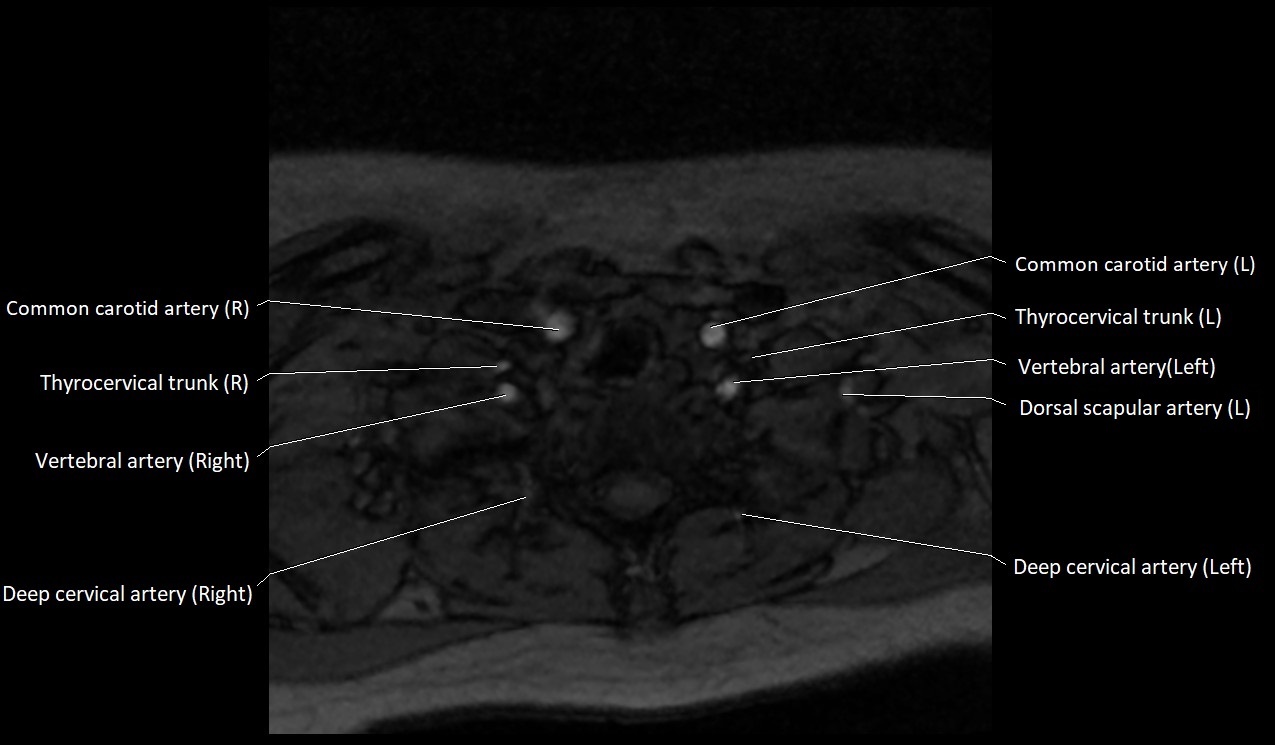

MRI Appearance:

• T1-Weighted Images:

• Appears as a tubular, hypointense (dark) structure relative to muscle

• May show flow void if the blood flow is fast

• T2-Weighted Images:

• Typically hypointense or isointense to muscle, but can be hyperintense if slow flow or stasis is present

MRI images